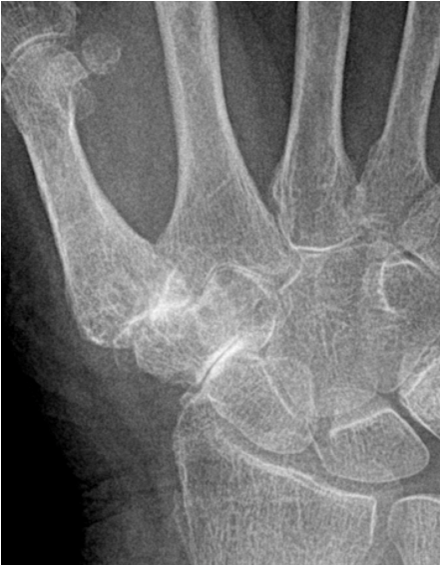

In the hand there is typically involvement of the trapezium-scaphoidal joint and the first carpal-metacarpal joint. In addition, there is involvement of the distal interphalangeal joints of the fingers with lesser changes at the proximal interphalangeal joints and the metacarpal-phalangeal joints.

Fig. 14. Typical degenerative changes in the hand: A) Joint space narrowing and subchondral sclerosis of the trapezoidum-scaphoidal joint and the first carpal-metacarpal joint. B.) Degenerative arthritis of the distal interphalangeal joint showing typical osteophyte formation, joint space narrowing and increased sclerosis.

In the foot there is often involvement of the first metatarsal-phalangeal joint. In addition to joint space narrowing and subchondral sclerosis there is subchondral degenerative cyst formation and osteophyte formation along joint margins. Osteophytes are the sine qua non of osteoarthritis. In degenerative joint disease new bone formation is seen as a response or repair reaction. In inflammatory arthritis there usually is a destruction of bone and osteophytes are not seen.